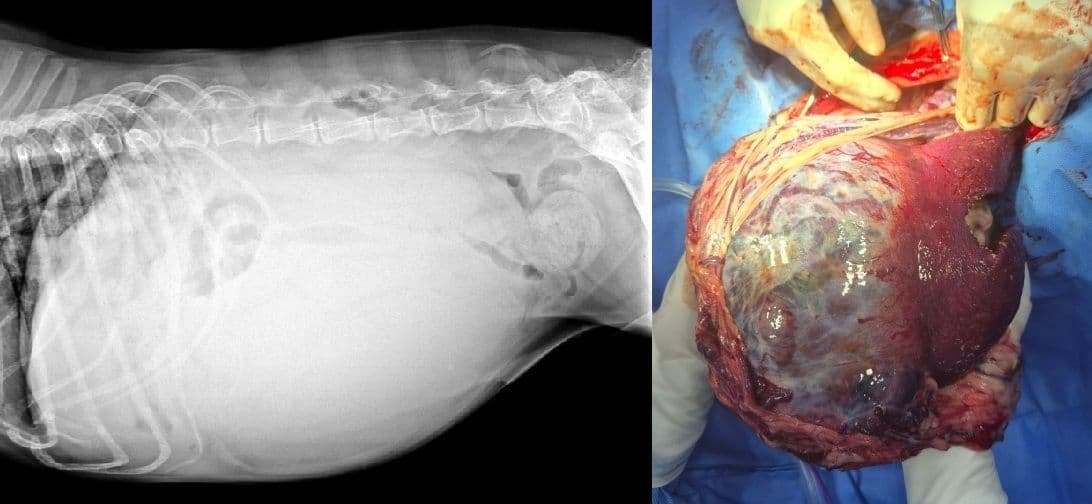

본원에서 진행된 각 장기별 실제 종양 확인 사례입니다.